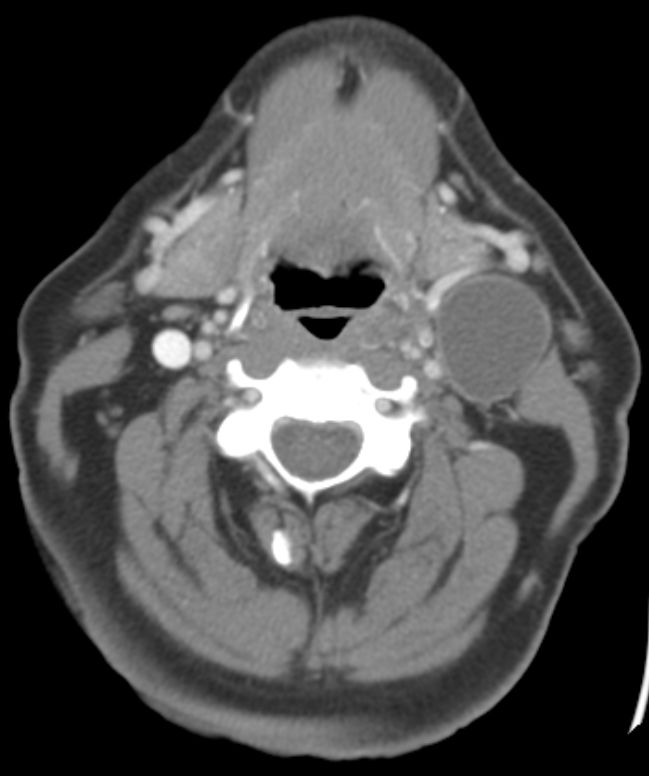

66-jähriger Mann mit einem zystischen 34mm großen Knoten links am Hals.

Die Panendoskopie ergab ein 11mm großes invasives Plattenepithelkarzinom der linken Tonsille. pT1 pN2a(1/15) Mo G3 p16+.  | |||